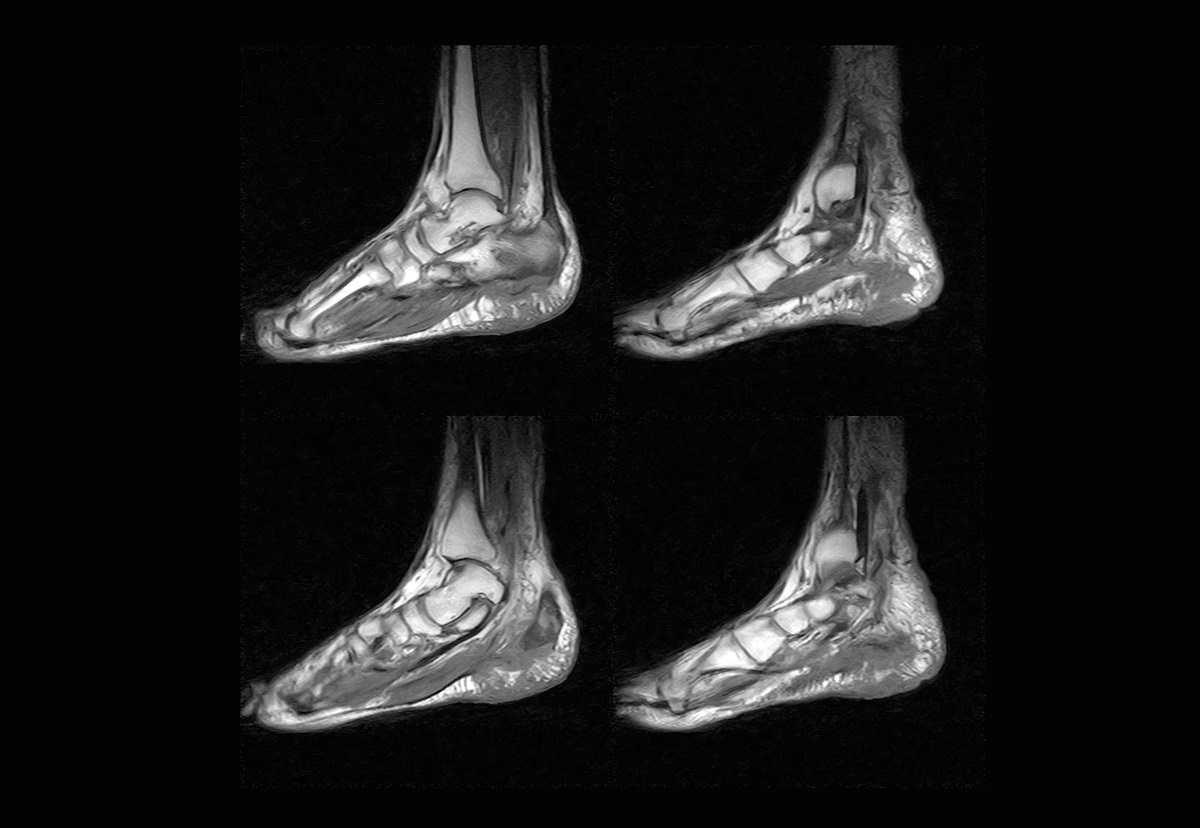

МСКТ, в отличие от обычного рентгена или стандартного КТ, позволяет получать детальные трехмерные изображения костей, суставных поверхностей, мягких тканей и сосудов стопы, а также голеностопного сустава.

Этот метод диагностики применяется при травмах, хронических воспалительных заболеваниях, подозрении на опухолевые процессы. Благодаря минимальной толщине среза и высокоточной визуализации врач получает максимально информативное изображение, что повышает точность постановки диагноза и позволяет выбрать оптимальную схему для дальнейшего лечения.

МСКТ стопы показывает даже минимальные изменения, которые не видны при стандартном рентгенологическом исследовании.

Исследование позволяет получать детализированные изображения костей и мягких тканей, выявлять скрытые переломы, ранние стадии заболеваний, недоступные для обычного рентгена.